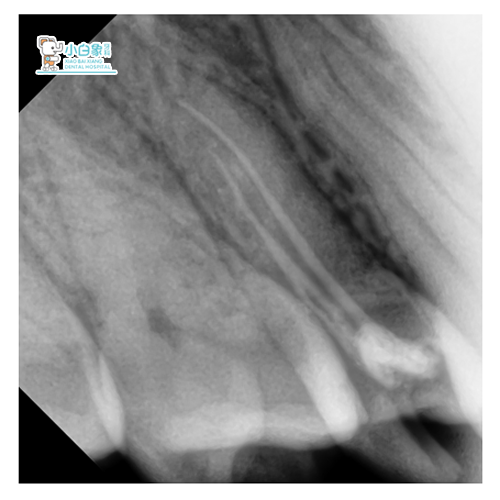

X线检查:根管内见高密度影欠填,根尖见低密度影。

诊断:15无髓牙/慢性根尖炎